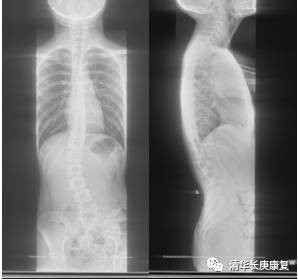

图1初诊X线显示: 脊柱下胸段及腰段有明显的侧弯,侧弯角度约有25°

李女士带着女儿到各大医院看诊,暂无手术指正,目前可进行保守治疗,动态观察脊柱侧弯进展。于是患儿来到我院康复医学科门诊,经过仔细康复评估,配置了个性化的脊柱矫形支具,并在治疗师一对一指导下进行姿势矫正康复训练,经过治疗,患儿脊柱侧弯角度明显减小了,并且其本人不适感也较以前明显缓解。

图2佩戴矫形支具后X线显示:偏移的胸段脊柱较治疗前靠近中线,侧弯角度明显减小。